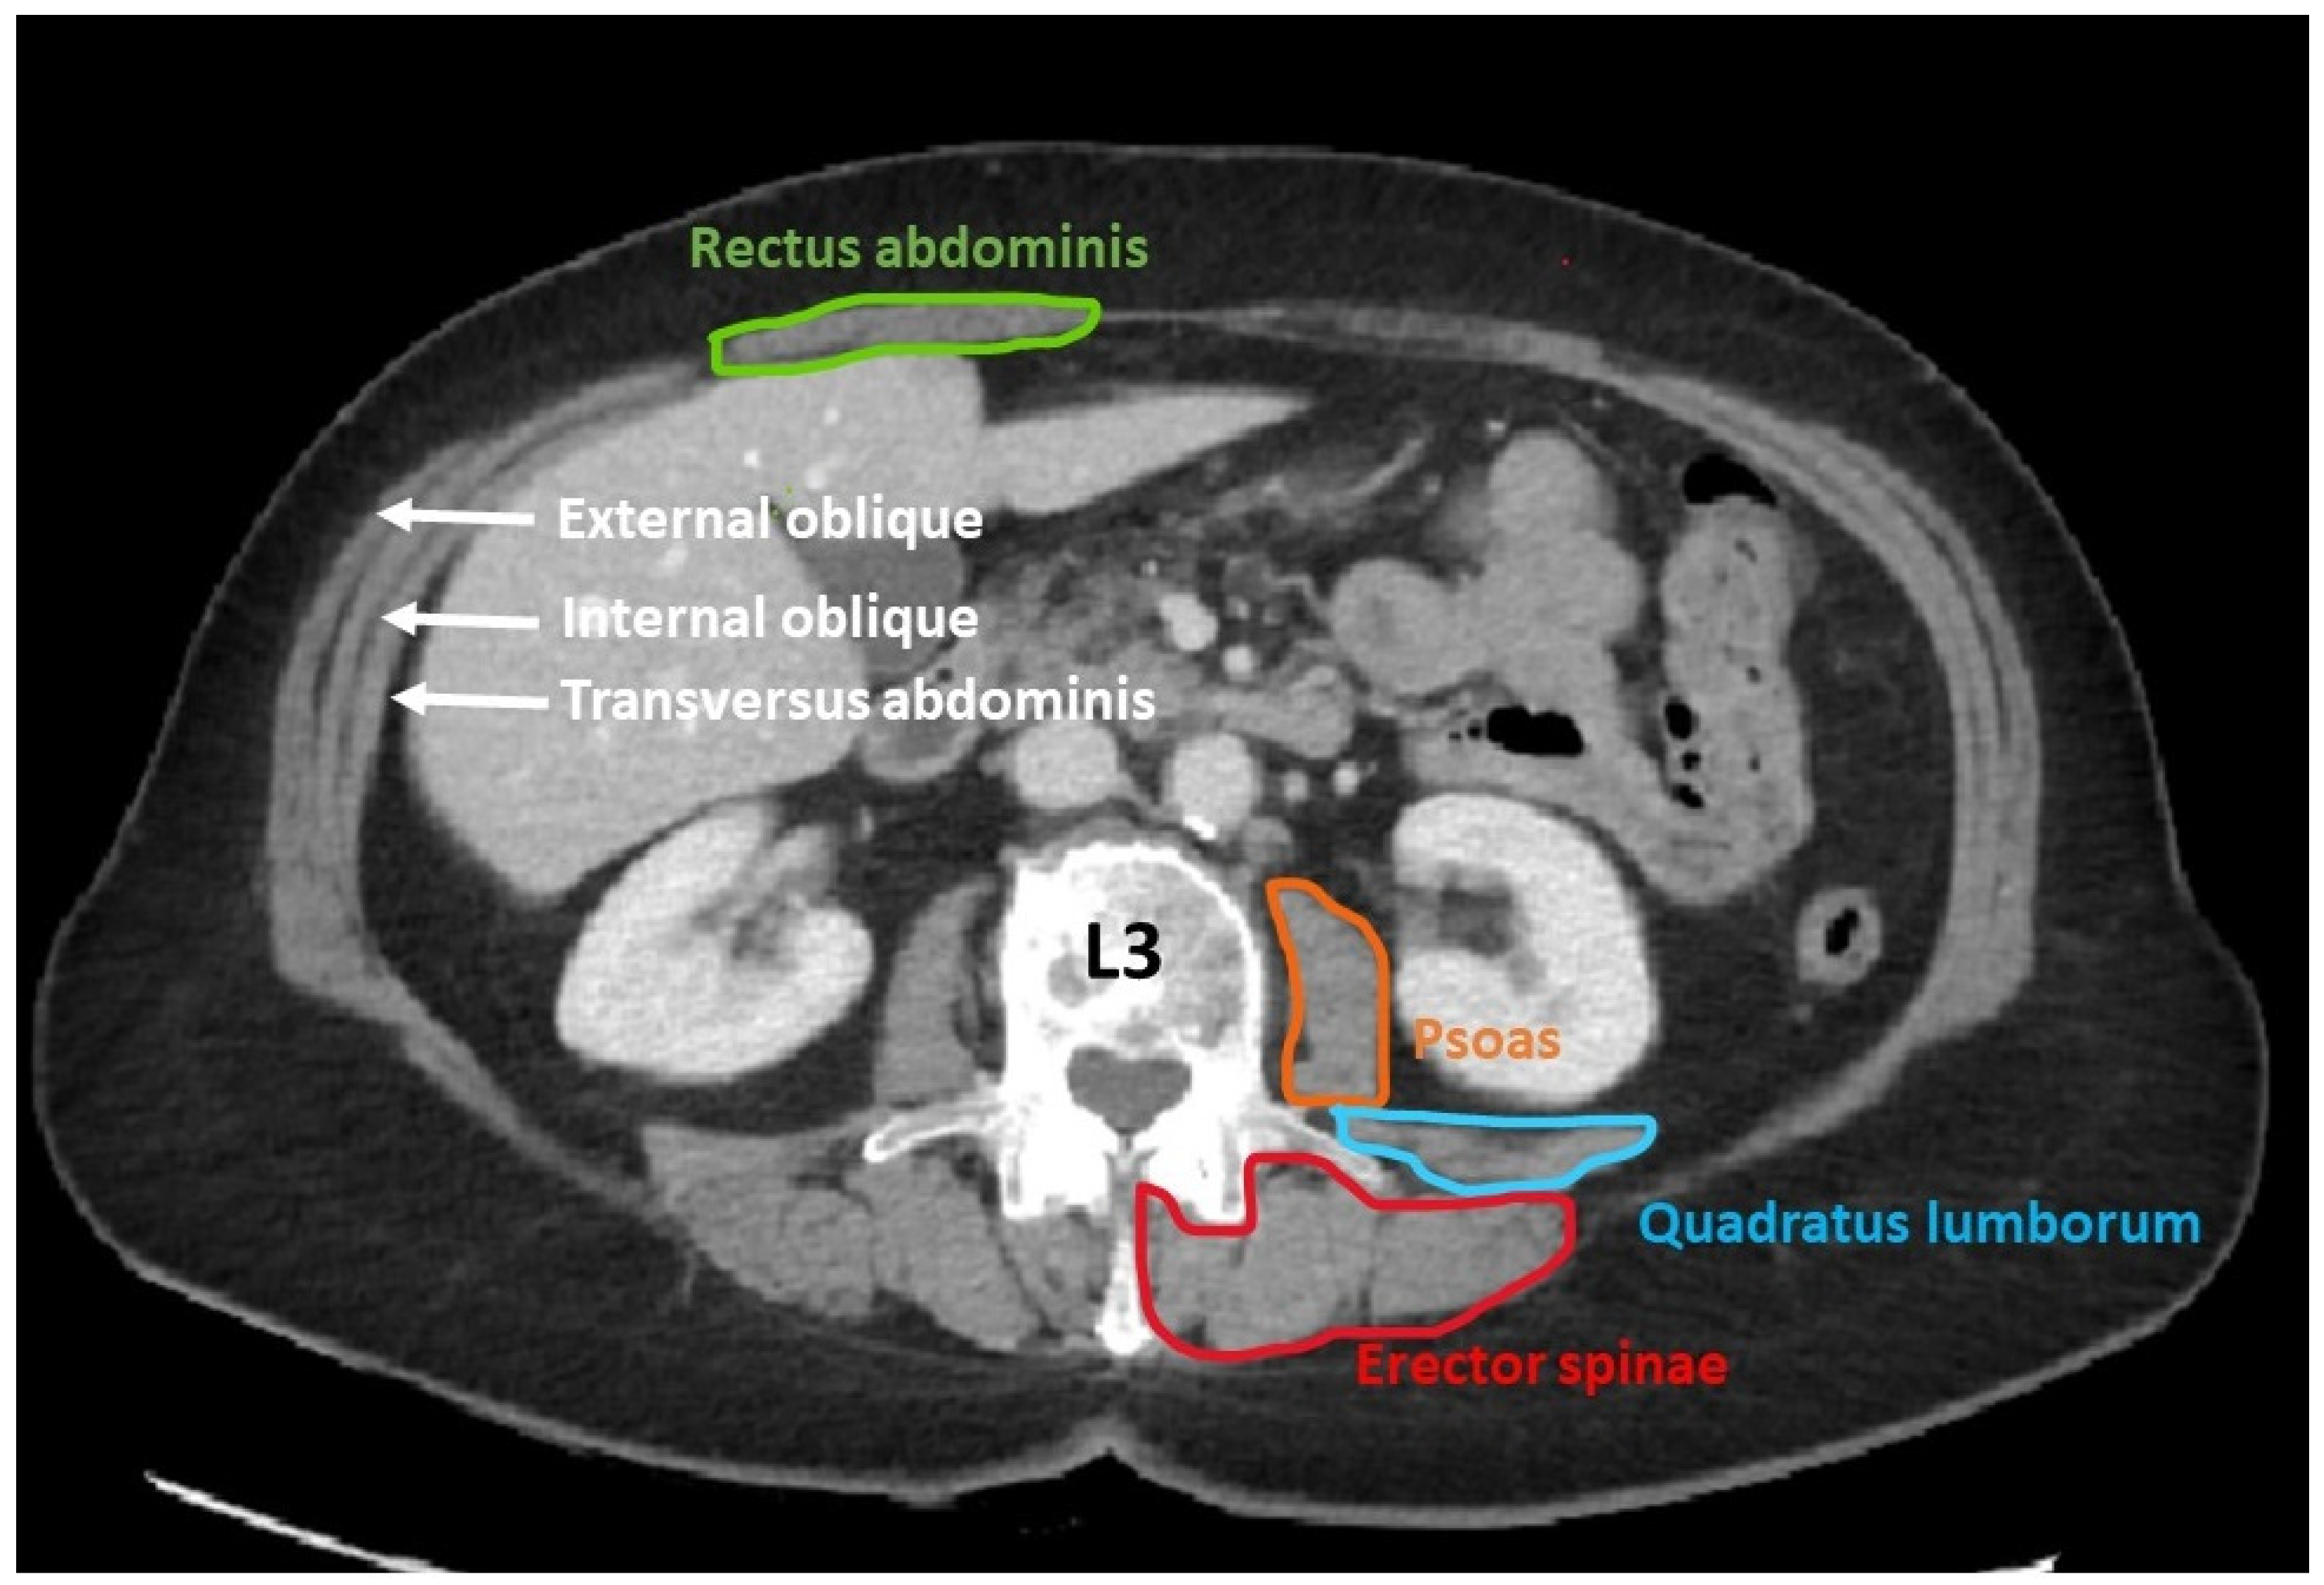

- Determination of muscle mass using computed tomography (CT scan)

- Gomez-Perez, S.L.; Haus, J.M.; Sheean, P.; Patel, B.; Mar, W.; Chaudhry, V.; McKeever, L.; Braunschweig, C. Measuring abdominal circumference and skeletal muscle from a single cross-sectional computed tomography image: A step-by-step guide for clinicians using National Institutes of Health ImageJ: A step-by-step guide for clinicians using national institutes of health ImageJ. JPEN J. Parenter. Enter. Nutr. 2016, 40, 308–318. [Google Scholar]